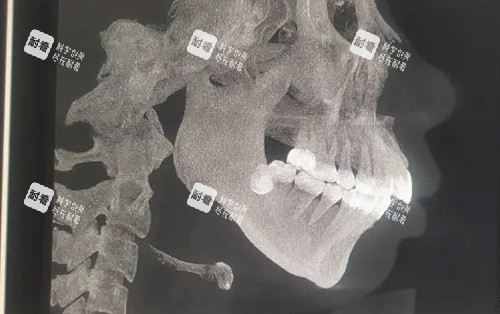

颏成型手术36800起,主要是针对下巴进行调整。下巴对一个人的面部美观影响可大啦!有些人下巴比较短,会显得面部比例不协调;还有些人下巴后缩,侧面看起来就不太好看。通过颏成型手术,就能让下巴变得更加较好。手术后,下巴的形态会更加自然,面部比例也会更加协调,从侧面看过去,整个面部线条都变得更加立体了。